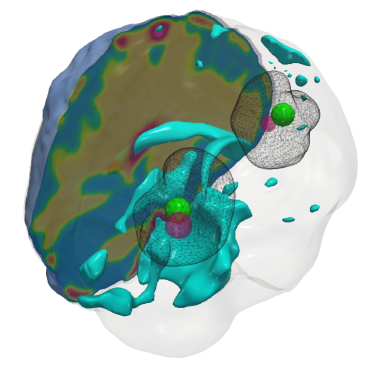

Fig. 5: Qualitative results for the artificial tumor test-case AT-C2 (a mono-focal tumor that has grown more and is infiltrative) with growth parameters ρ=12,κ=0.05formulae-sequencesuperscript𝜌12superscript𝜅0.05\rho^{\star}=12,~{}\kappa^{\star}=0.05. The images show the tumor data (gray wireframe), ground truth tumor initial condition (green volume), reconstructed tumor initial condition (magenta volume), ventricles (cyan volume), and a section of the patient brain geometry. As with smaller tumors, the \mathboldL2\mathboldsubscript𝐿2\mathbold{L_{2}} solver predicts an initial condition reconstruction that has a large support and lacks localization capabilities. Hence, the solver is unable to determine the reaction coefficient accurately. While sparsity constraints help in localizing the initial condition, an exact initial condition reconstruction is difficult due to the ill-conditioned inverse problem.

Setup. We grow synthetic tumors in the segmentation of a statistical brain atlas [8] MRI scan (an atlas obtain by averaging several MR images). The segmentation labels are gray matter, white matter, and cerebrospinal fluid-filled ventricles (CSF). We use sparse initial conditions to grow the tumor to a significant size resembling clinical observations and invert for all biophysical parameters using the grown tumor at t=1𝑡1t=1 as input data to the solver. For all our test cases, we assume that the tumor grows and diffuses only in white matter. For this test-case, we observe the data everywhere, i.e., cd=0subscript𝑐𝑑0c_{d}=0. We consider the following variations:

(i) AT-C1: medium sized, mono-focal tumor ρ=8superscript𝜌8\rho^{\star}=8 κ=0.025superscript𝜅0.025\kappa^{\star}=0.025

(ii) AT-C2: large sized, mono-focal tumor ρ=12superscript𝜌12\rho^{\star}=12 κ=0.05superscript𝜅0.05\kappa^{\star}=0.05

(iii) AT-C3: multi-focal tumor, nearby seeds ρ=10superscript𝜌10\rho^{\star}=10 κ=0.025superscript𝜅0.025\kappa^{\star}=0.025

(iv) AT-C4: multi-focal tumor, distant seeds ρ=8superscript𝜌8\rho^{\star}=8 κ=0.025superscript𝜅0.025\kappa^{\star}=0.025

We report our quantitative results (performance measures, convergence, and solver timings) in Tab. 4 and visualize the reconstruction to qualitatively assess the performance of our solvers in Fig. 4 - Fig. 7. Each figure shows an isometric view of the patient brain with 3D volumes of the grown tumor data, ground truth, and reconstructed initial condition. We additionally visualize the ventricles and sections of healthy tissue to reveal the heterogeneity of the brain (and hence the tumor).

Observations. We observe that for the medium sized tumor (AT-C1) the reconstruction is nearly perfect for the CS solver while the \mathboldL2\mathboldsubscript𝐿2\mathbold{L_{2}} solver produces a lower performance, particularly in the inversion of the reaction coefficient. This is primarily due to the rich initial conditions produced by the \mathboldL2\mathboldsubscript𝐿2\mathbold{L_{2}} solver which impedes its ability to predict the correct reaction scaling using our method. We note that if the reaction scaling is known beforehand, the \mathboldL2\mathboldsubscript𝐿2\mathbold{L_{2}} solver can potentially have better performance (see [56, 16] for similar synthetic experiments). This problem is magnified for larger tumors (AT-C2 and AT-C3) where the predicted reaction coefficient shows about 66%percent6666\% and 54%percent5454\% relative error in the \mathboldL2\mathboldsubscript𝐿2\mathbold{L_{2}} solver for the two test-cases respectively (as compared to around 15%percent1515\% and 1%percent11\% error with sparsity constraints). The reconstruction in diffusivity also suffers similarly without enforcing sparsity. The final test-case shows a multi-focal tumor with two far apart proliferation sites. While both the solvers produce disjoint initial conditions for the tumor, the CS solver does better in reconstructing the model parameters: 2% versus 37% relative error in diffusivity and 9% versus 50% relative error in reaction coefficient. Both solvers show similar performance in their ability to fit the data (as measured by the relative error in final tumor reconstruction). Hence, our synthetic observations show consistent improvement in target parameter estimation for all test-cases with sparse initial conditions, without sacrificing the final tumor reconstruction quality.